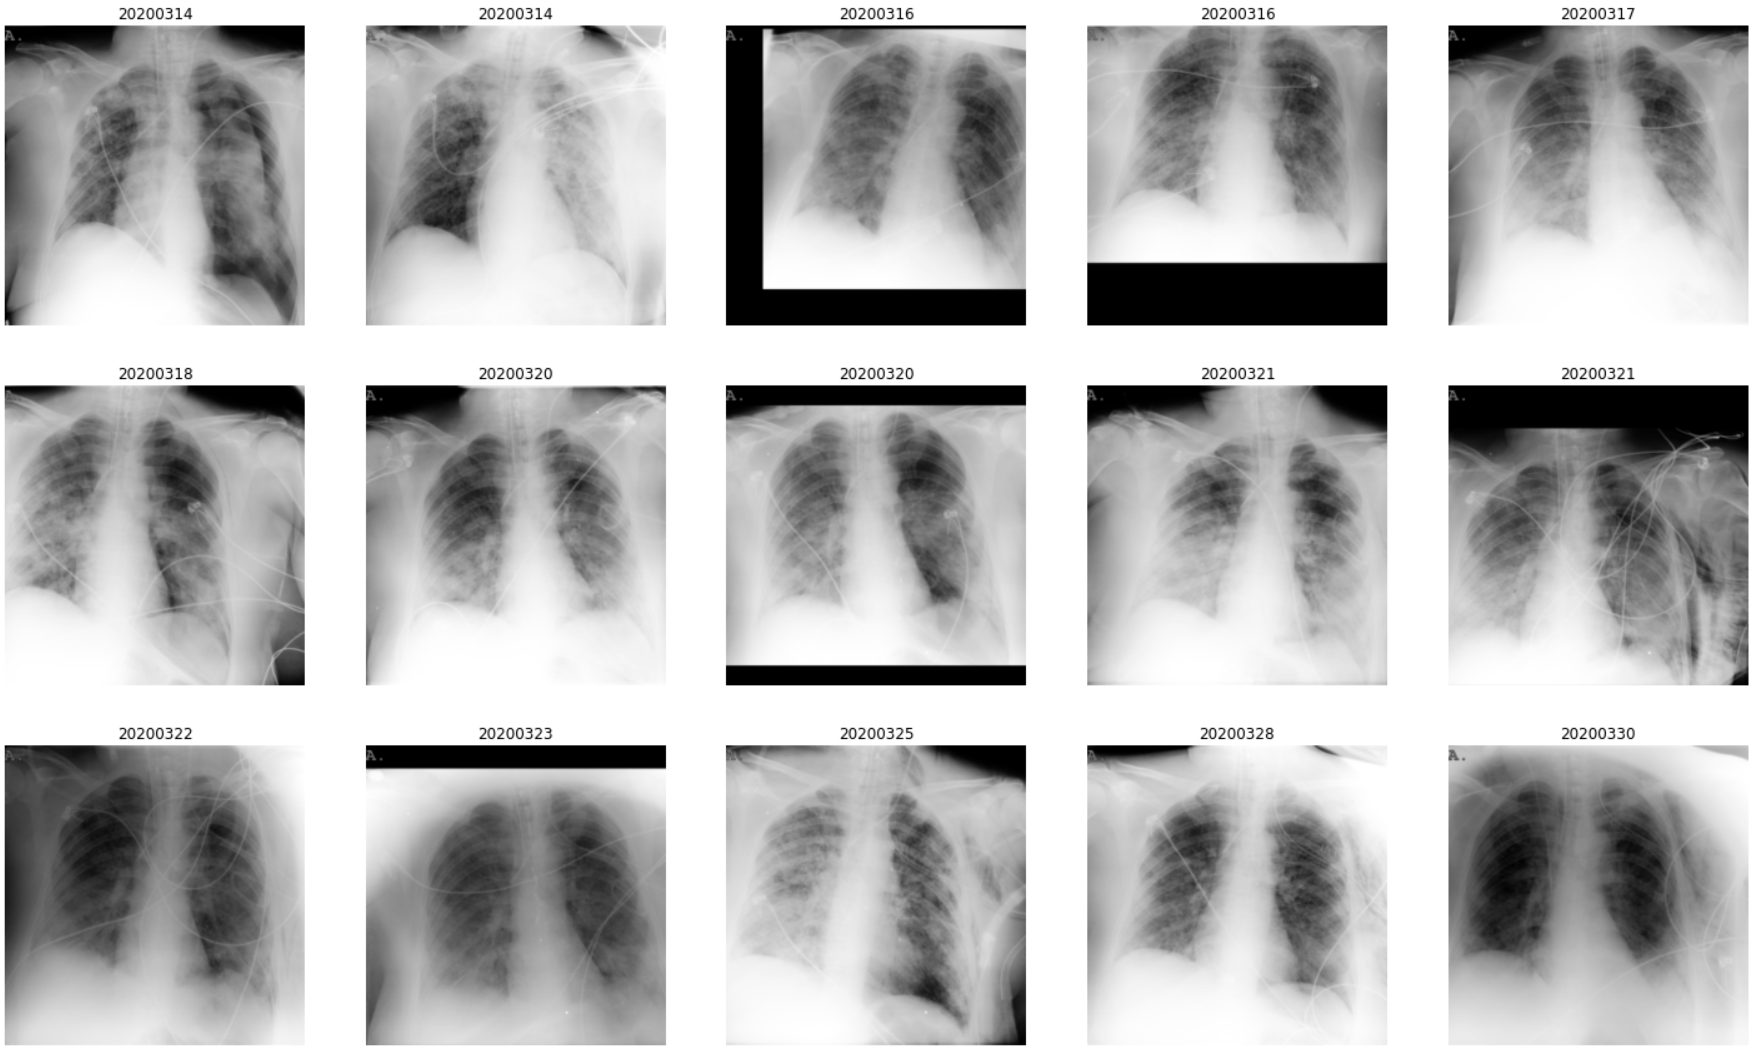

Beyond labeling an image as COVID/No/Others as occurs with most existing datasets, it is, therefore, very important to annotate the radiological findings, for both the diagnosis and the prognosis. It should be considered that these characteristic lesions frequently appear in non-COVID patients and that, on the contrary, many COVID-19 patients do not have these lesions. The appearance of the lesions is related to the level of the disease. It is characteristic that many of the patients worsen and that lesions appear or become more evident.

To the best of our knowledge, BIMCV COVID-19+ is the first COVID-19 dataset that includes these findings. In addition, in this first iteration, ten images were also annotated with the ROIs of the findings.

Since some lesions such as infiltrates, ground glass opacities or consolidation patterns are the most frequent in COVID-19 patients, a sub-set of 10 images were annotated with their ROIs by a team of eight radiologists from the Hospital Universitario de San Juan de Alicante, for the first iteration of the BIMCV COVID-19+ dataset.